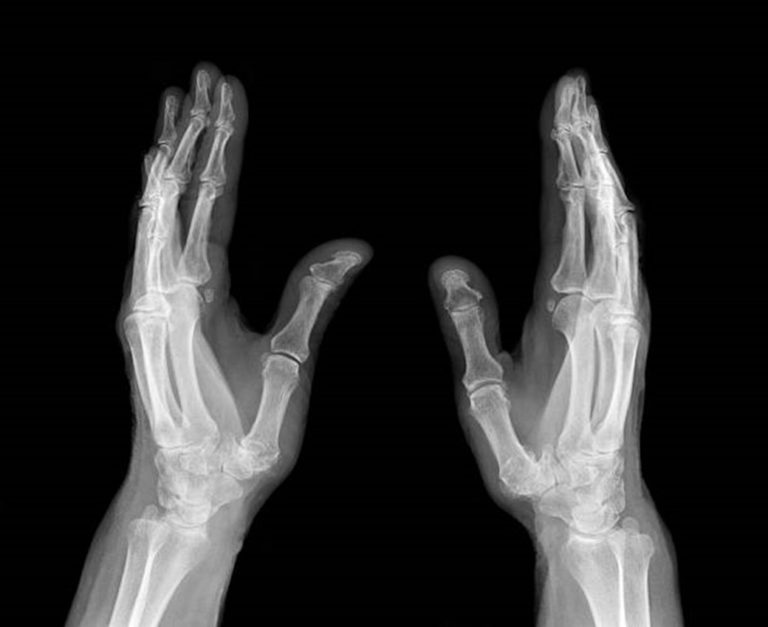

Kezünk egészsége és megfelelő működése mindennapi életünk egyik legfontosabb feltétele. A kéz funkciójának bármilyen megváltozása – legyen szó betegségről, sérülésről vagy elváltozásról – jelentősen ronthatja életminőségünket és mindennapi tevékenységeinket. A kézsebészet a sebészet egyik speciális területe, amely a kéz, a csukló, az alkar és részben a könyök betegségeinek, sérüléseinek diagnosztizálásával és kezelésével foglalkozik. Célja a kéz mozgásának, erejének és érzékelésének helyreállítása, ezáltal a mindennapi életben való teljes értékű részvétel biztosítása.

Leggyakoribb kézbetegségek